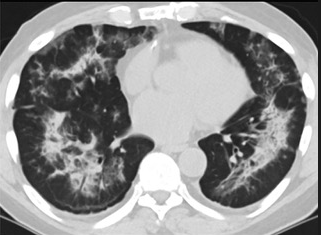

怎么“中度可疑”呢?这些专家表示,这5位患者的肺部CT都具备新冠肺炎CT的影像特征,比如肺部出现磨玻璃的影像,磨玻璃主要分布在双下肺靠近外周,出现铺路石征、严重的表现为双肺弥漫性多发实变。同时,其病程转归和临床特征也与新冠肺炎相似。

以下面这4张图涉及的这个美国“电子烟”病人为例,专家不是仅仅通过一张影片做判断的,而是通过这4张涵盖了这名病例肺部多天变化情况的影片进行的研判,认为该病例的病程进展跟新冠更为相似。